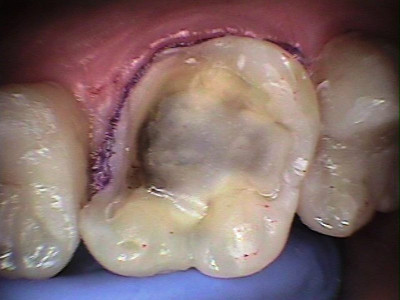

Inicio. Molar con extensa fractura